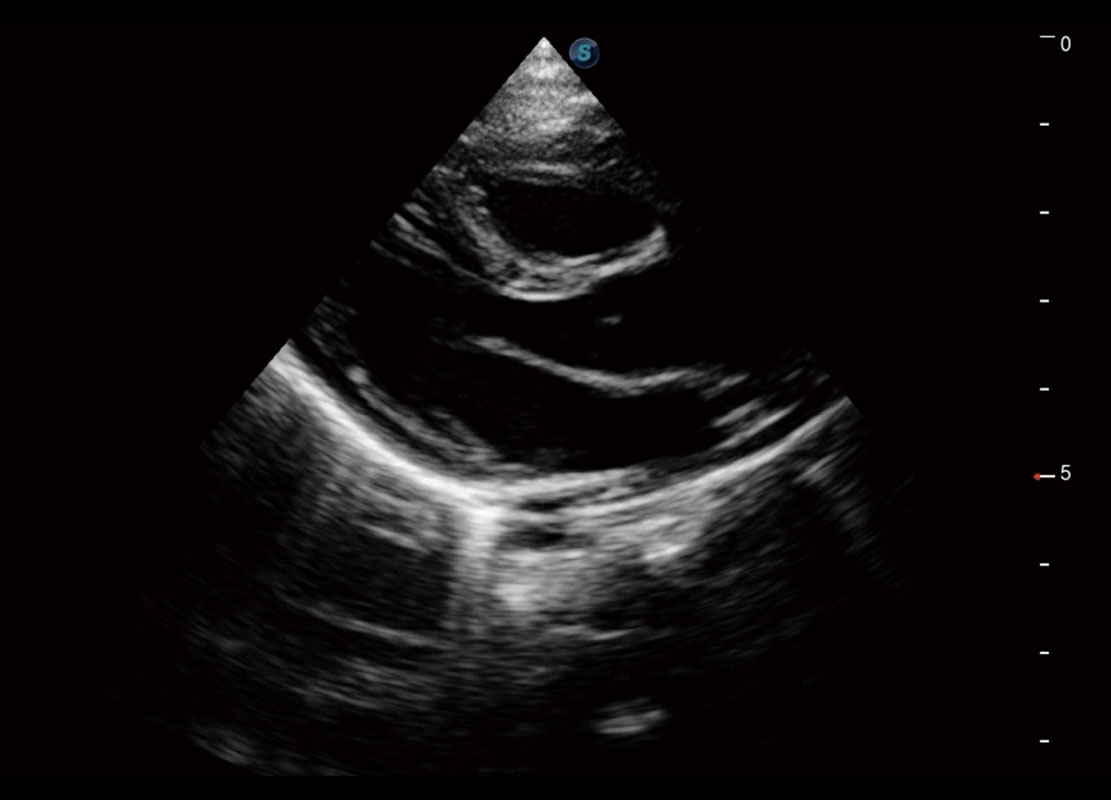

胎心筛查

P60搭载一系列胎儿心脏成像技术,实现更精细的胎儿心脏评估。

• 四腔切面

• 四腔心血流

• 右室双出口

• 胎心容积成像